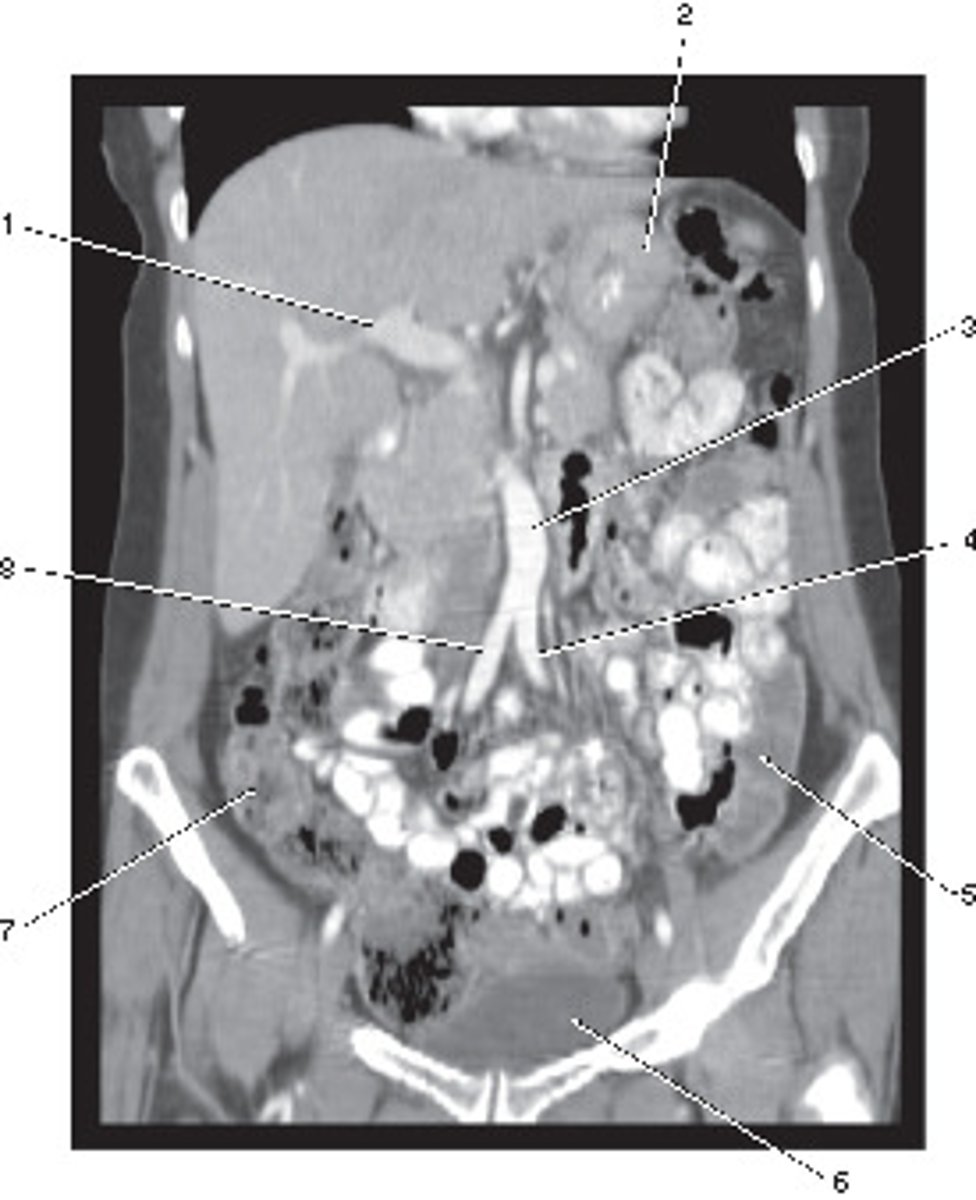

Portal Vein

Number 1 corresponds to which of the following?

<p>Number 1 corresponds to which of the following?</p>

Superior Mesenteric Artery

Stomach

Number 2 corresponds to which of the following?

<p>Number 2 corresponds to which of the following?</p>